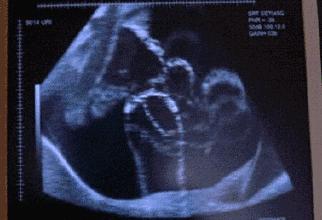

肚子尖生男孩,圆生女孩?

准妈妈肚皮的形状,取决于胎位、妈妈的体形、骨盆宽窄。

肚子尖的多是枕后位,宝宝的脸、胸、肚子朝向妈妈肚皮,当他们活动的时候,小手和小脚常常会在妈妈肚皮一侧拱啊拱的,所以就显得肚子尖咯。